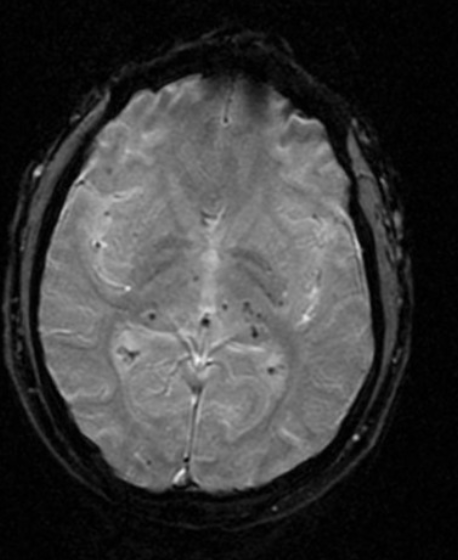

Microhemorragias hipertensivas

cerebelo, tálamo, ponte, núcleos da base